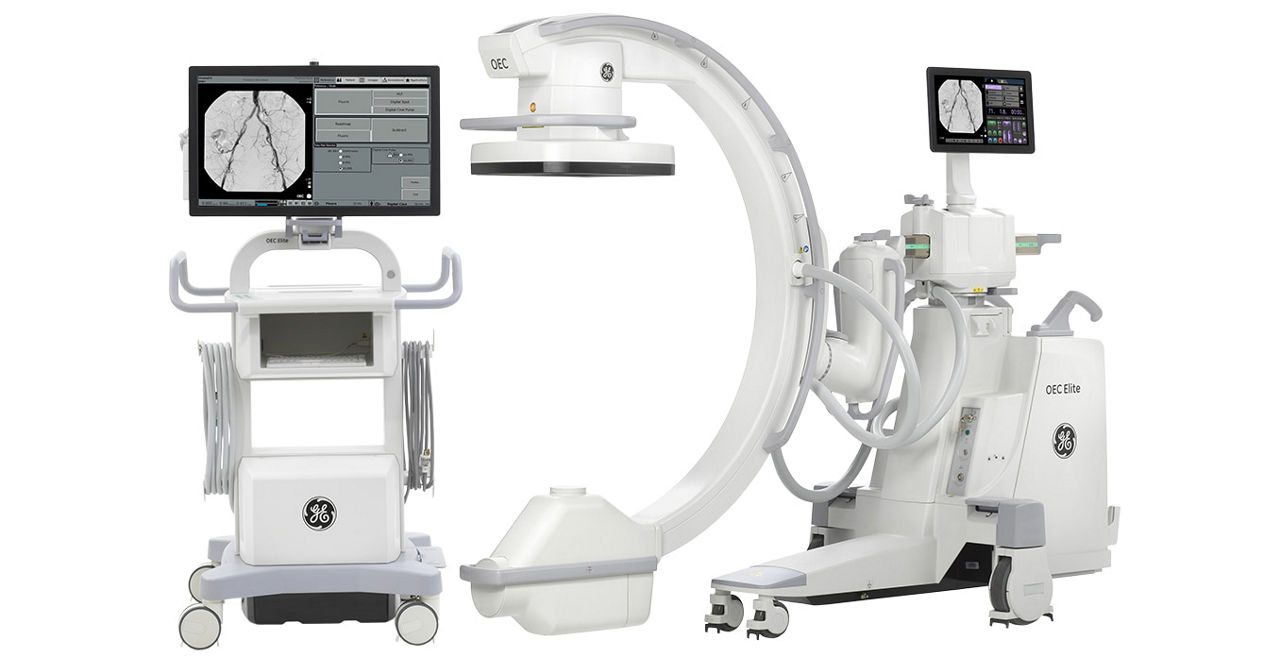

Leveraging transformational imaging technology to realize the promise of precision medicine and help deliver better outcomes. Our medical imaging products range from systems, including MRI, CT, PET, SPECT, Ultrasound, Mammography and X-ray, to digital and AI solutions to help drive healthcare digitialization, help enable faster exam workflow, improve clinical outcomes and increase efficiencies.